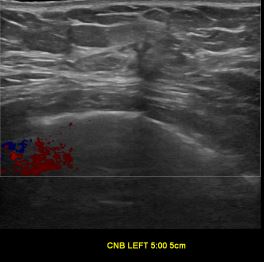

상기환자는 외부검사 이상소견으로 내원하신 60대초반 여성분으로 의심스러운 좌측혹 조직검사 시행해 유방암으로 진단되었습니다